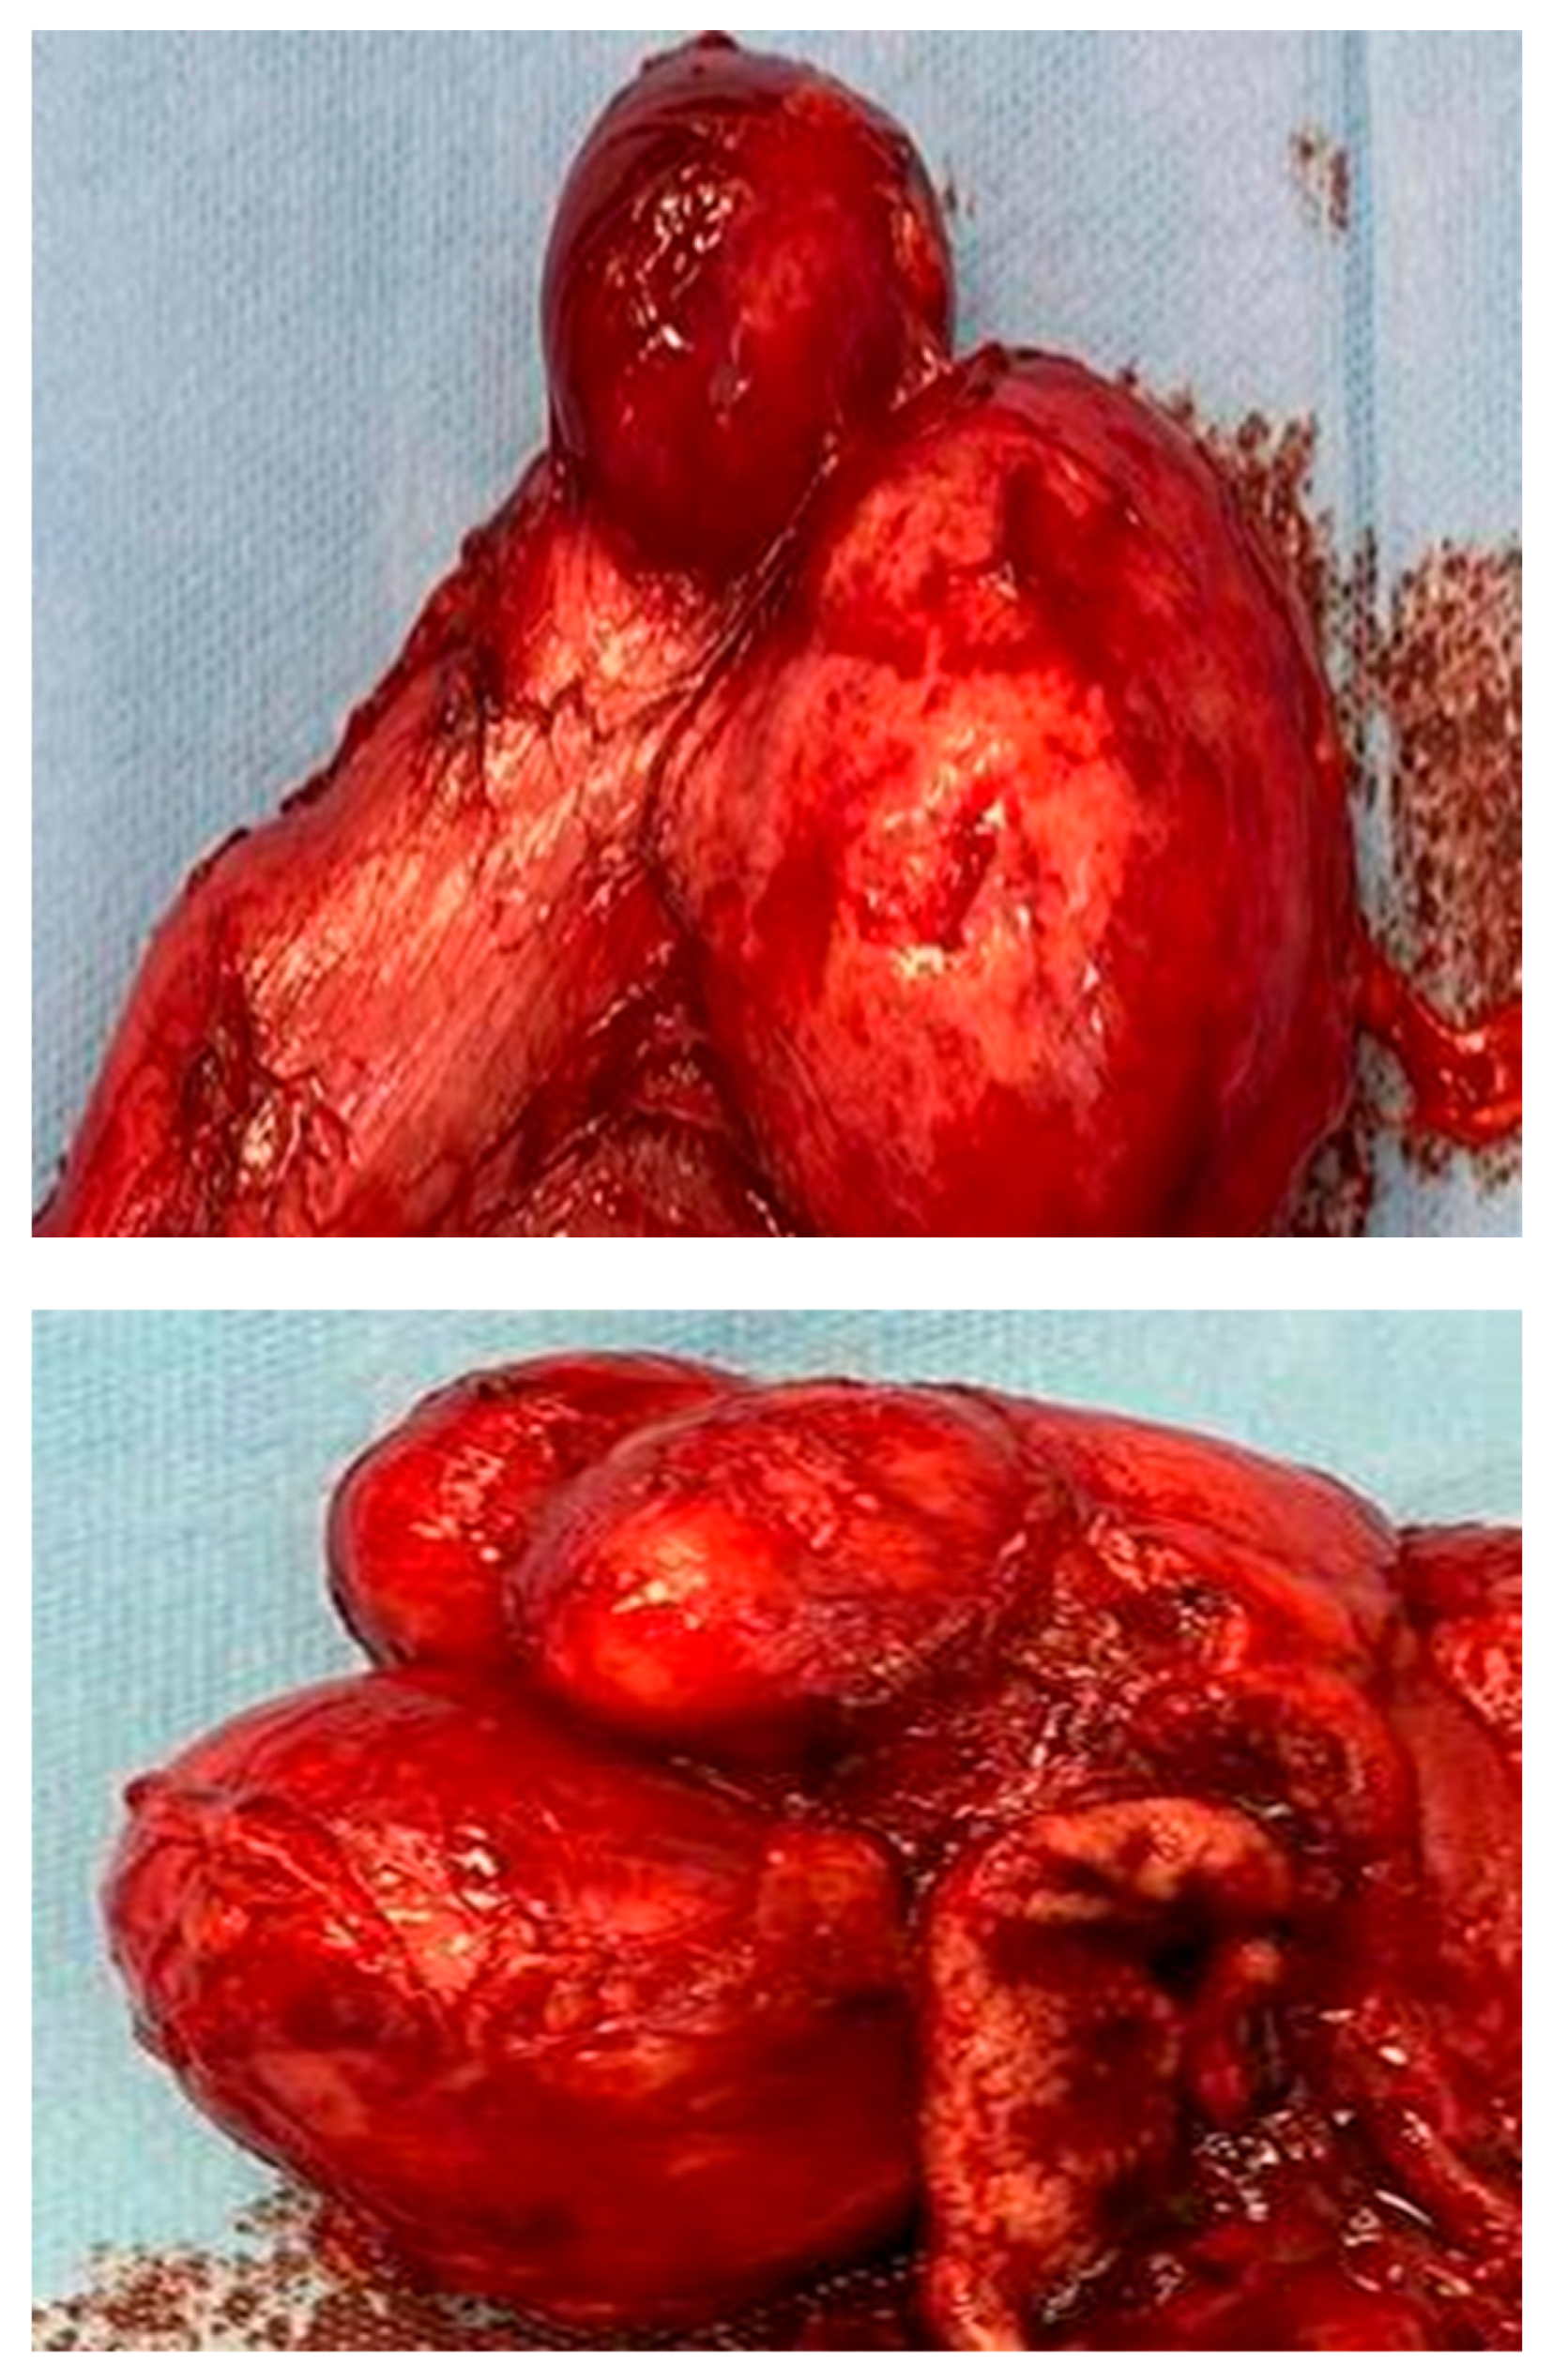

2.1. Surgery

2.2. Histopathological Result